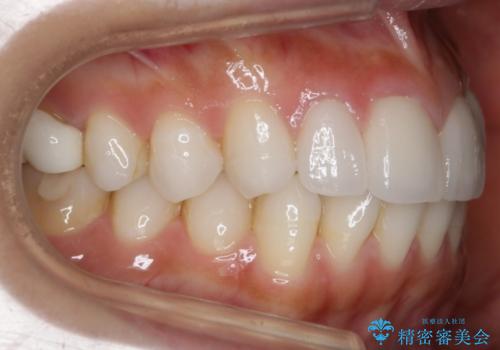

【非抜歯】噛み合わせを整えたい! インビザライン矯正

- 嚙み合わせのズレを主訴にご来院されました。

前歯・奥歯ともにセラミッククラウンで治療されている歯があったため、その歯にあまり影響が出ない範囲内で全体の噛み合わせが良くなるような動きを組み込んで治療を進めることとなりました。